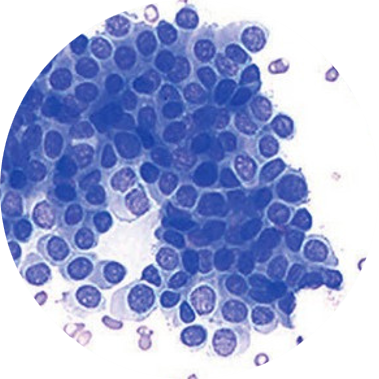

Exame Imuno-Histoquímico

Imuno-histoquímica é a técnica que aplica anticorpos específicos presentes em cortes histológicos, em associação com métodos de detecção altamente sensíveis para revelação da ligação antígeno (em geral, marcador tumoral) e anticorpo.

A aplicação desta técnica, em associação com a experiencia do patologista como morfologista, tem grande auxilio na definição diagnóstica e na definição de melhor tratamento para os pacientes.

O Lapac dispõe de uma variedade de anticorpos que permite avaliação diagnostica, prognostica e preditiva nas mais diversas patologias. As principais indicações clínico diagnósticas para o exame de Imuno-histoquímico são:

- Classificação de carcinomas;

- Classificação de neoplasias indiferenciadas;

- Marcadores de carcinoma mamário;

- Classificação de linfomas, neoplasias linfo reticulares e hematopoiéticas;

- Baterias específicas para classificação de tumores;

- Marcadores para determinação de malignidade em lesões suspeitas;

- Pesquisa de micrometástases em linfonodo;

- Pesquisa de agentes etiológicos e microbiológicos;

- Carcinomas metastáticos de origem indeterminada;

- Classificação de carcinomas;

- Classificação de neoplasias indiferenciadas;

- Marcadores de carcinoma mamário;

- Classificação de linfomas, neoplasias linfo-reticulares e hemotopoéticas.